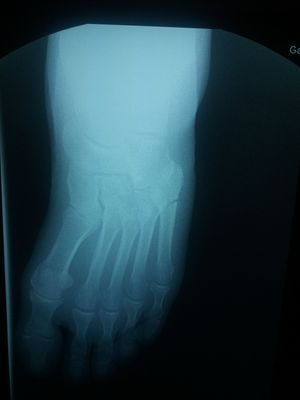

Trauma

Foot

Rentgen

Jones fracture